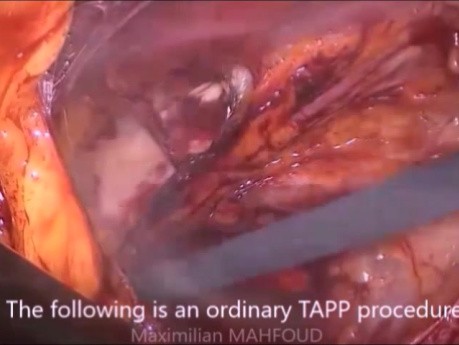

Tratamiento laparoscópico de la hernia inguinal...

¿Quién estaría dispuesto a abordar una hernia inguinal estrangulada por acceso directo después de dos reparaciones abiertas? La mejor opción en estos casos sería la reducción + reparación herniaria...